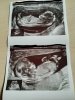

My po prenatalnych🤩 z USG wszystko super, z ciekawostek wczoraj lekarz powiedział że chyba chłopak a dzisiaj pani doktor, że wg niej dziewczynka 🤪😅 ale dzisiaj mi pokazała ten wyrostek płciowy i faktycznie nic nie odstawał 🤷😃 Na pappa też muszę czekać ok. 2 tyg. Dostanę na mejla, ale jestem dobrej myśli 🙂🙂 termin na 10 kwietnia 🙂

Załączniki

• IMG_20201001_114640.jpg

IMG_20201001_114640.jpg

1,5 MB · Wyświetleń: 99